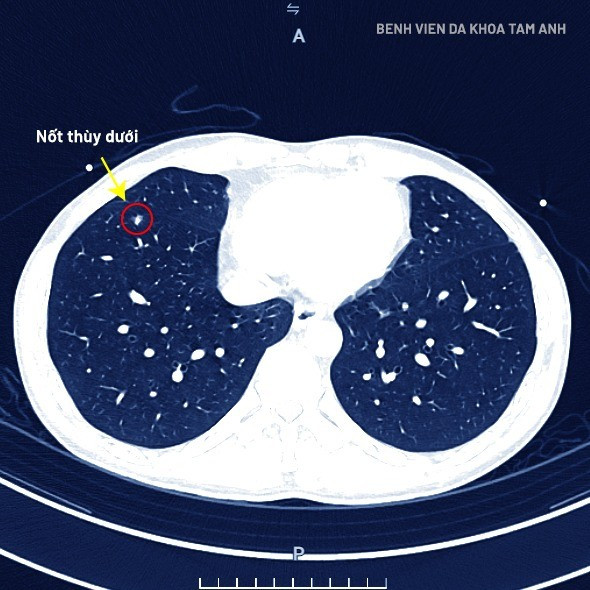

Kết quả chụp CT Somatom Force VB30 phát hiện: Nốt đặc nguy cơ cao thùy dưới phổi phải, kích thước 4,5 x 7,6mm, bờ không đều, có dấu hiệu co kéo màng phổi; phân loại LUNG-RADS 4X - nhóm nguy cơ ác tính cao.

Bệnh nhân chụp CT Somatom Force VB30 phát hiện ung thư phổi giai đoạn sớm - Ảnh BVCC